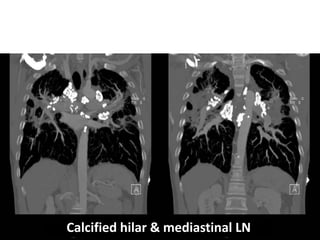

Atypical

LN calcification

(amorphus, punctate, popcorn or eggshell calcification).

DD of calcified hilar or mediastinal LN

• Silicosis

• Sarcoidosis.

• TB.

• Treated lymphoma.

Calcified hilar & mediastinal LN